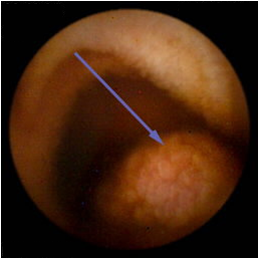

⑤ESD

随着内镜微创技术的发展,越来越多的早期消化道癌、癌前病变及胃肠黏膜下疾病可完全在内镜下予以切除,免除了更大的手术创伤,这就是内镜黏膜下剥离术ESD(endoscopic submucosal dissecfion)

该治疗具有不改变消化道解剖结构、不开刀、体表无创口、创伤、出血少、恢复快等优势,是近年来国际、国内最新兴起的内窥镜下微创治疗手段之一,适用于食管、胃、十二指肠等上消化道及结、直肠的黏膜下良性肿瘤、黏膜的早期癌变以及具有癌变倾向病变的切除治疗。因其特殊的微创优势,得到广大医生及患者的推崇,是消化道黏膜及黏膜下病变治疗的新兴发展趋势。我中心已经开展该项技术,技术成熟,并还开展了经口内镜下肌切开术POEM、内镜经粘膜下隧道肿瘤切除术STER、粘膜下隧道内镜剥离术ESTD,术后病人随访,恢复良好。

Ⅰ、ESD的治疗效果如何?

ESD治疗胃早癌可实现较高的整块切除率(92%~97%)和完整切除率(73.6%~94.7%),5年总生存率和5年疾病生存率分别为96.2%~97.1%和100%。